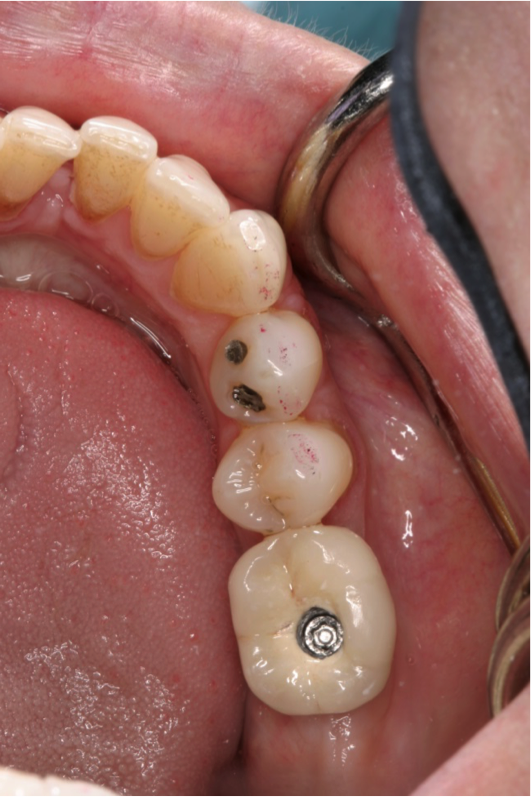

The patient wanted an implant-supported crown to restore the right mandibular first molar, which had been extracted after recurrent caries, endodontic treatment, and development of a periapical lesion. The site was grafted with bone grafting material and a biological membrane and allowed to heal for 6 months. A periapical radiograph was then taken (Figure 6), which showed the socket areas to be well condensed, with mature-looking bone. A CBCT scan was taken to facilitate implant-placement planning.

Fig 6. Periapical radiograph, single missing tooth.

Figure 6